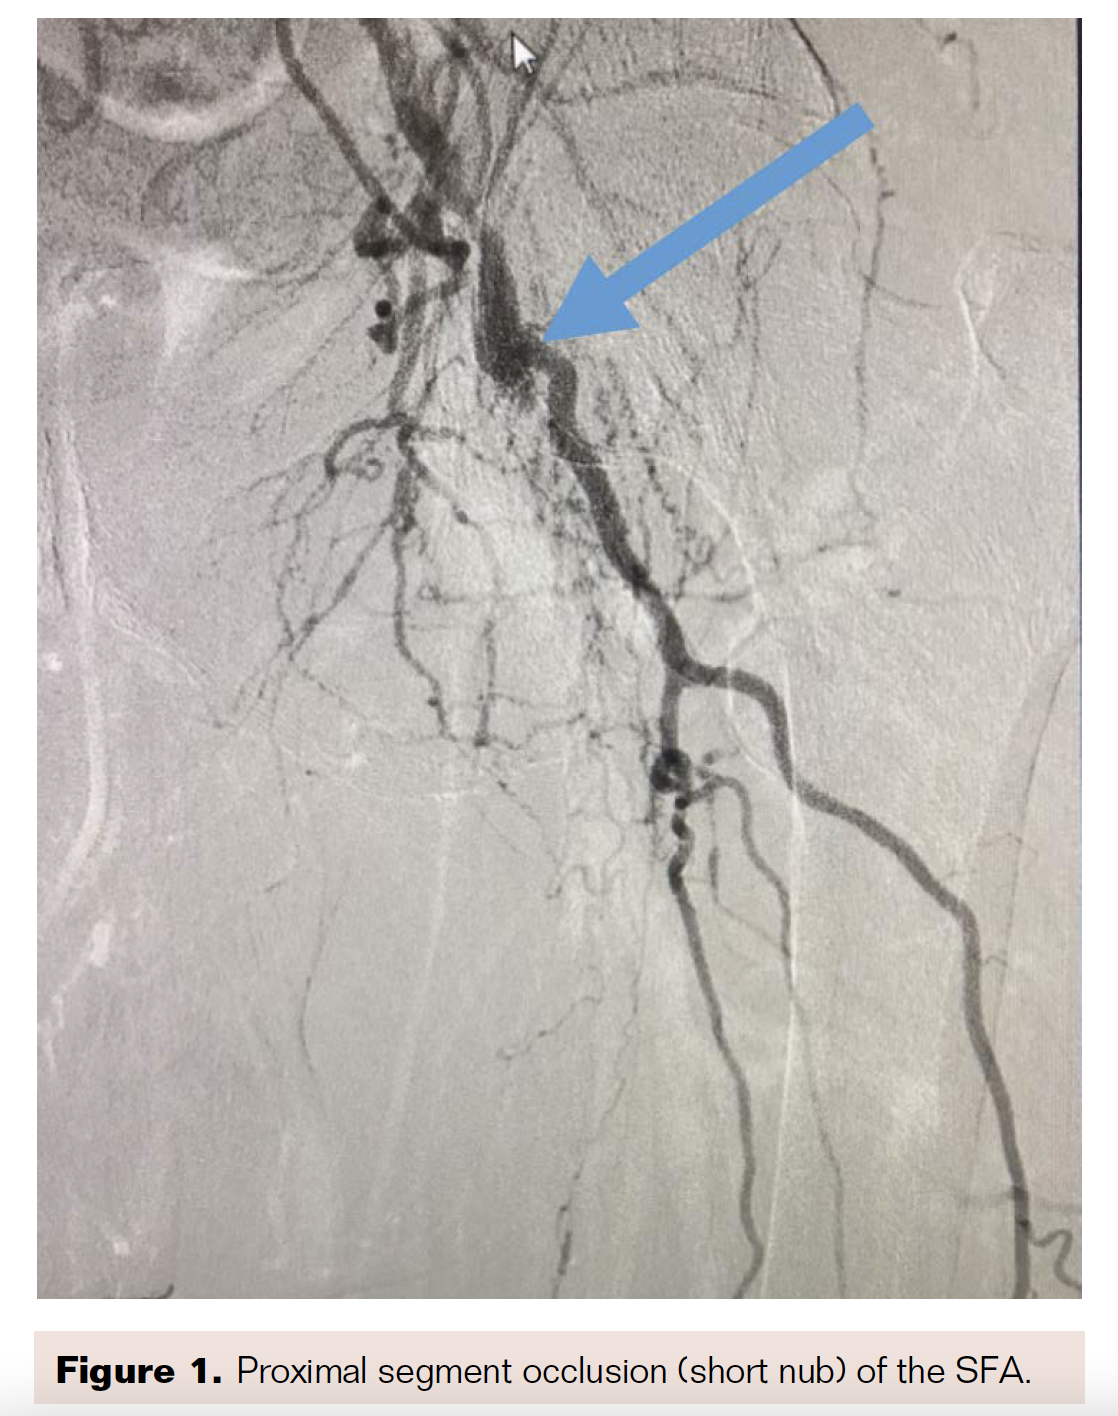

6 × 100 mm Zilver PTX stent (Cook Medical) was placed distal to the Viabahn covered stent, resulting in <10% residual stenosis and successfully tacking up the dissection (Figure 8). We then addressed the 99% distal popliteal/tibioperoneal (TP) trunk stenosis (Figure 9). We performed PTA of the TP trunk stenosis with a 4 × 28 mm Coronary Trek Balloon (Abbott), bringing the 99% stenosis to <20% residual stenosis (Figure 10) and improving the two-vessel flow to the foot (Figure 11).